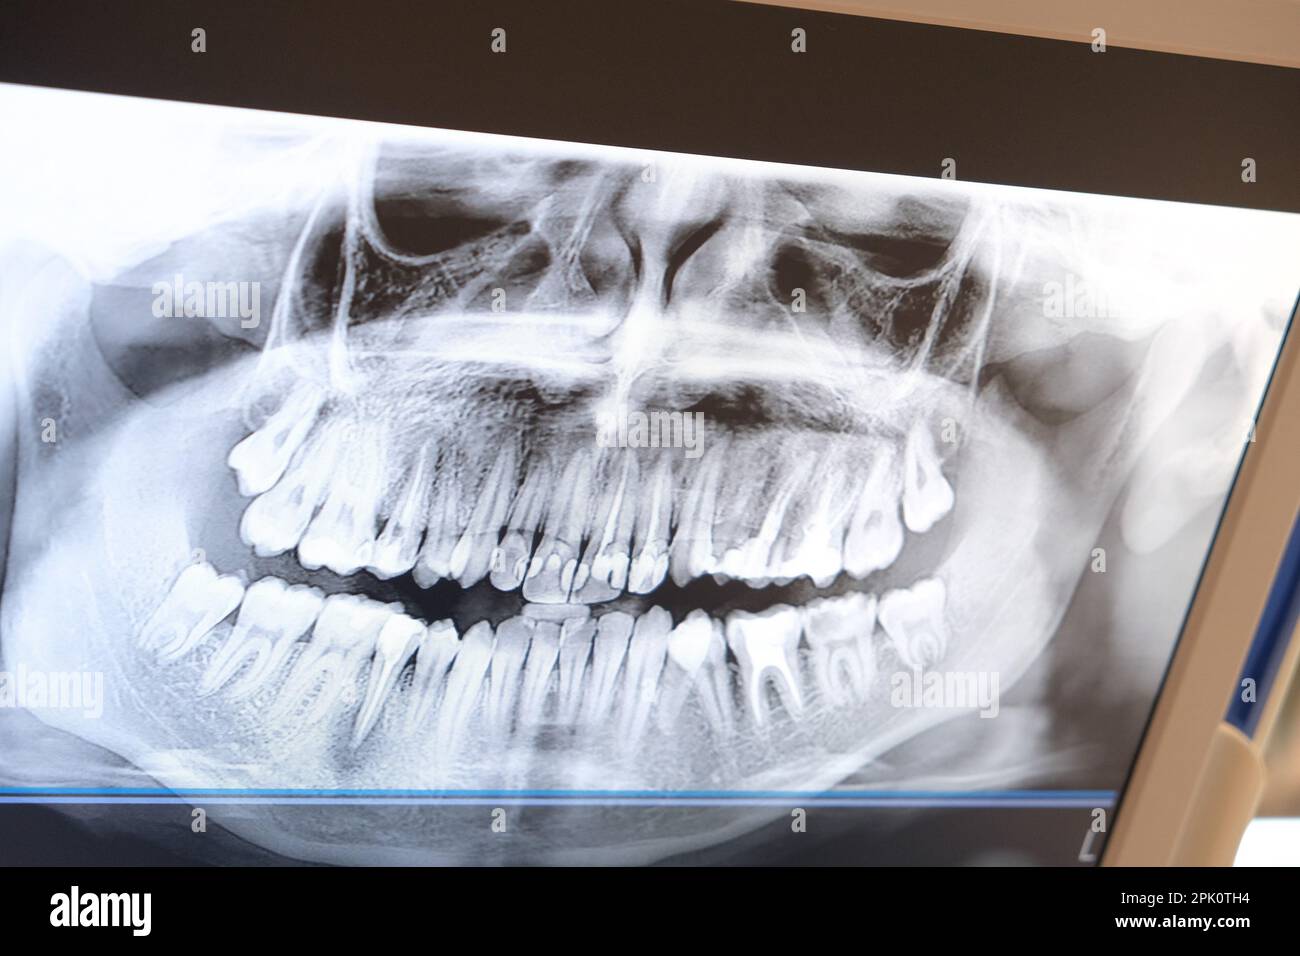

Ghost Image Dental X Ray . Table 5 lists various errors that can occur with. For example, in the edentulous patient having relatively thin. the present study sought to present a study of the formation of panoramic radiograph ghost images caused by metal objects in. it is important for the clinician to be able to understand errors when they occur and how to correct them. while ghost images of some anatomic structures cannot be avoided, most ghost images can be ex cluded or reduced. in an article on ghost images, monsour and mendoza carried out a study with a metal ball while mapping the ghost. panoramic images are difficult to interpret as, apart from the usual images of jaws. many ghost images are actually from normal anatomic structures.

it is important for the clinician to be able to understand errors when they occur and how to correct them. while ghost images of some anatomic structures cannot be avoided, most ghost images can be ex cluded or reduced. many ghost images are actually from normal anatomic structures. For example, in the edentulous patient having relatively thin. panoramic images are difficult to interpret as, apart from the usual images of jaws. in an article on ghost images, monsour and mendoza carried out a study with a metal ball while mapping the ghost. Table 5 lists various errors that can occur with. the present study sought to present a study of the formation of panoramic radiograph ghost images caused by metal objects in.